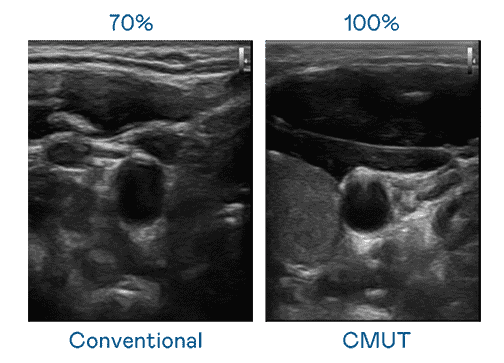

CMUT 技术是一种用电容式微机电元件来产生超音波讯号的技术。。。与传统 PZT 压电式技术相比,,CMUT 频宽增加 30%,,,更宽频的超音波讯号让影像解析度大幅提升,,,是实现高影像品质医疗超音波扫描、、促进精准医疗发展的关键技术。。

大频宽带来超清晰影像

超音波影像的解析度高低,,,首先取决于探头能发出的讯号频宽。。云顶国际8588yd CMUT 可提供高清晰的超音波讯号,,提供高频宽、、高灵敏度、、影像纹理细节更高的超音波影像,,,,协助医护人员缩短影像判读时间及利用精准的医疗影像进行诊断。。。